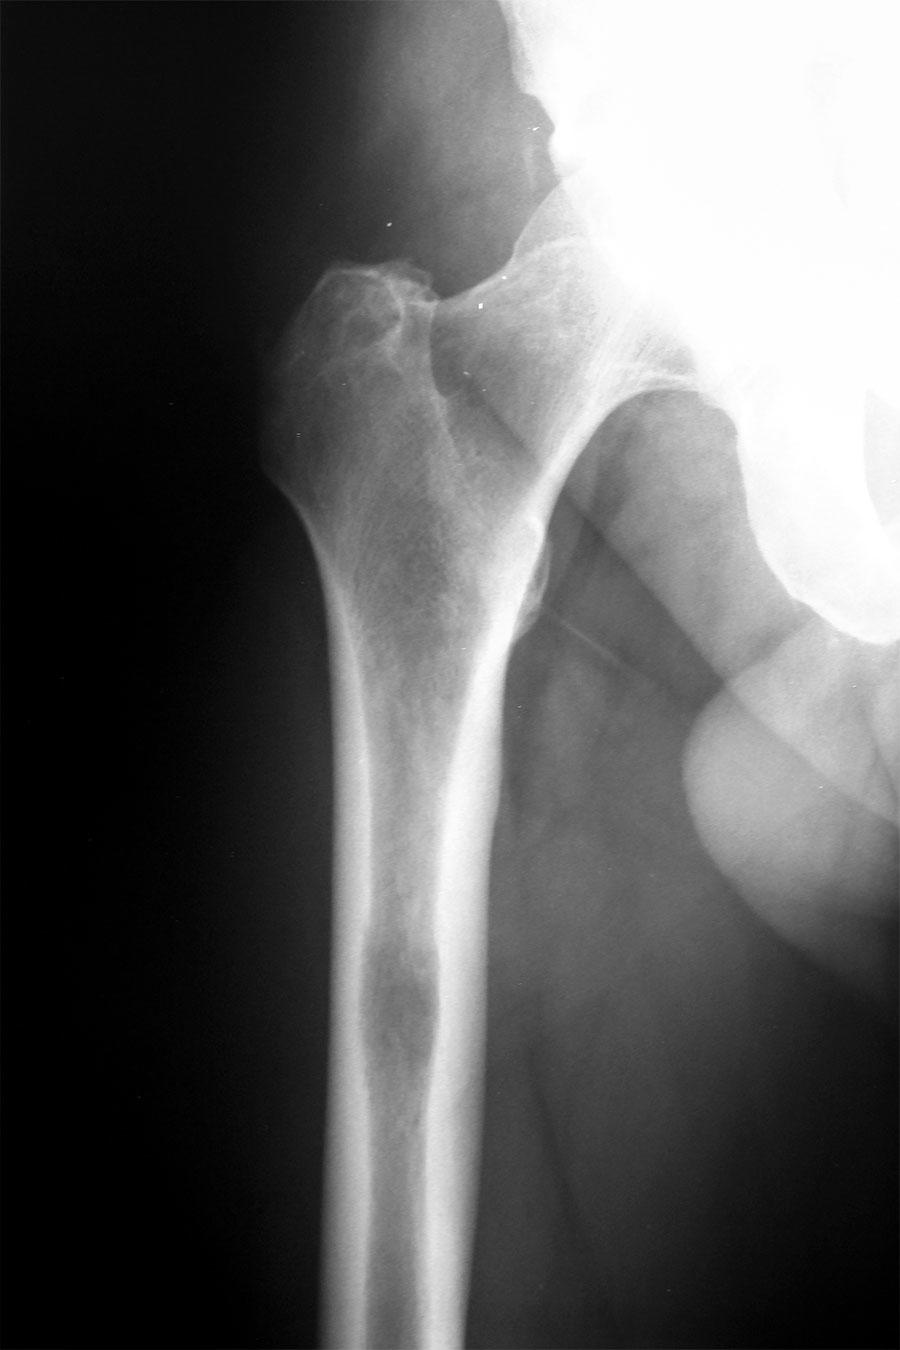

X-ray image showing the hip and upper thigh bone area, revealing a metastatic tumor that has spread to the bone tissue.

For patients with cancer that has spread to their bones, a single dose of radiation therapy may treat bone pain as effectively as a series of lower doses of radiation delivered over multiple days, according to the results of a clinical trial.

When cancer spreads, tumor cells frequently travel to bone, sometimes causing debilitating pain. Radiation therapy has long been used to shrink metastatic bone tumors to help relieve this pain, but no consensus has been reached about the optimal dose of such palliative radiation and whether it should be delivered in a single dose or in multiple treatments.